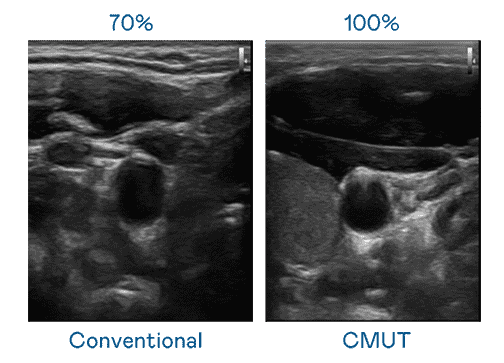

CMUT 技术是一种用电容式微机电元件来产生超音波讯号的技术。。。。与传统 PZT 压电式技术相比,,,CMUT 频宽增加 30%,,,更宽频的超音波讯号让影像解析度大幅提升,,,,是实现高影像品质医疗超音波扫描、、促进精准医疗发展的关键技术。。。。

大频宽带来超清晰影像

超音波影像的解析度高低,,首先取决于探头能发出的讯号频宽。。。。汇旺支付 CMUT 可提供高清晰的超音波讯号,,,,提供高频宽、、高灵敏度、、、、影像纹理细节更高的超音波影像,,,,协助医护人员缩短影像判读时间及利用精准的医疗影像进行诊断。。。